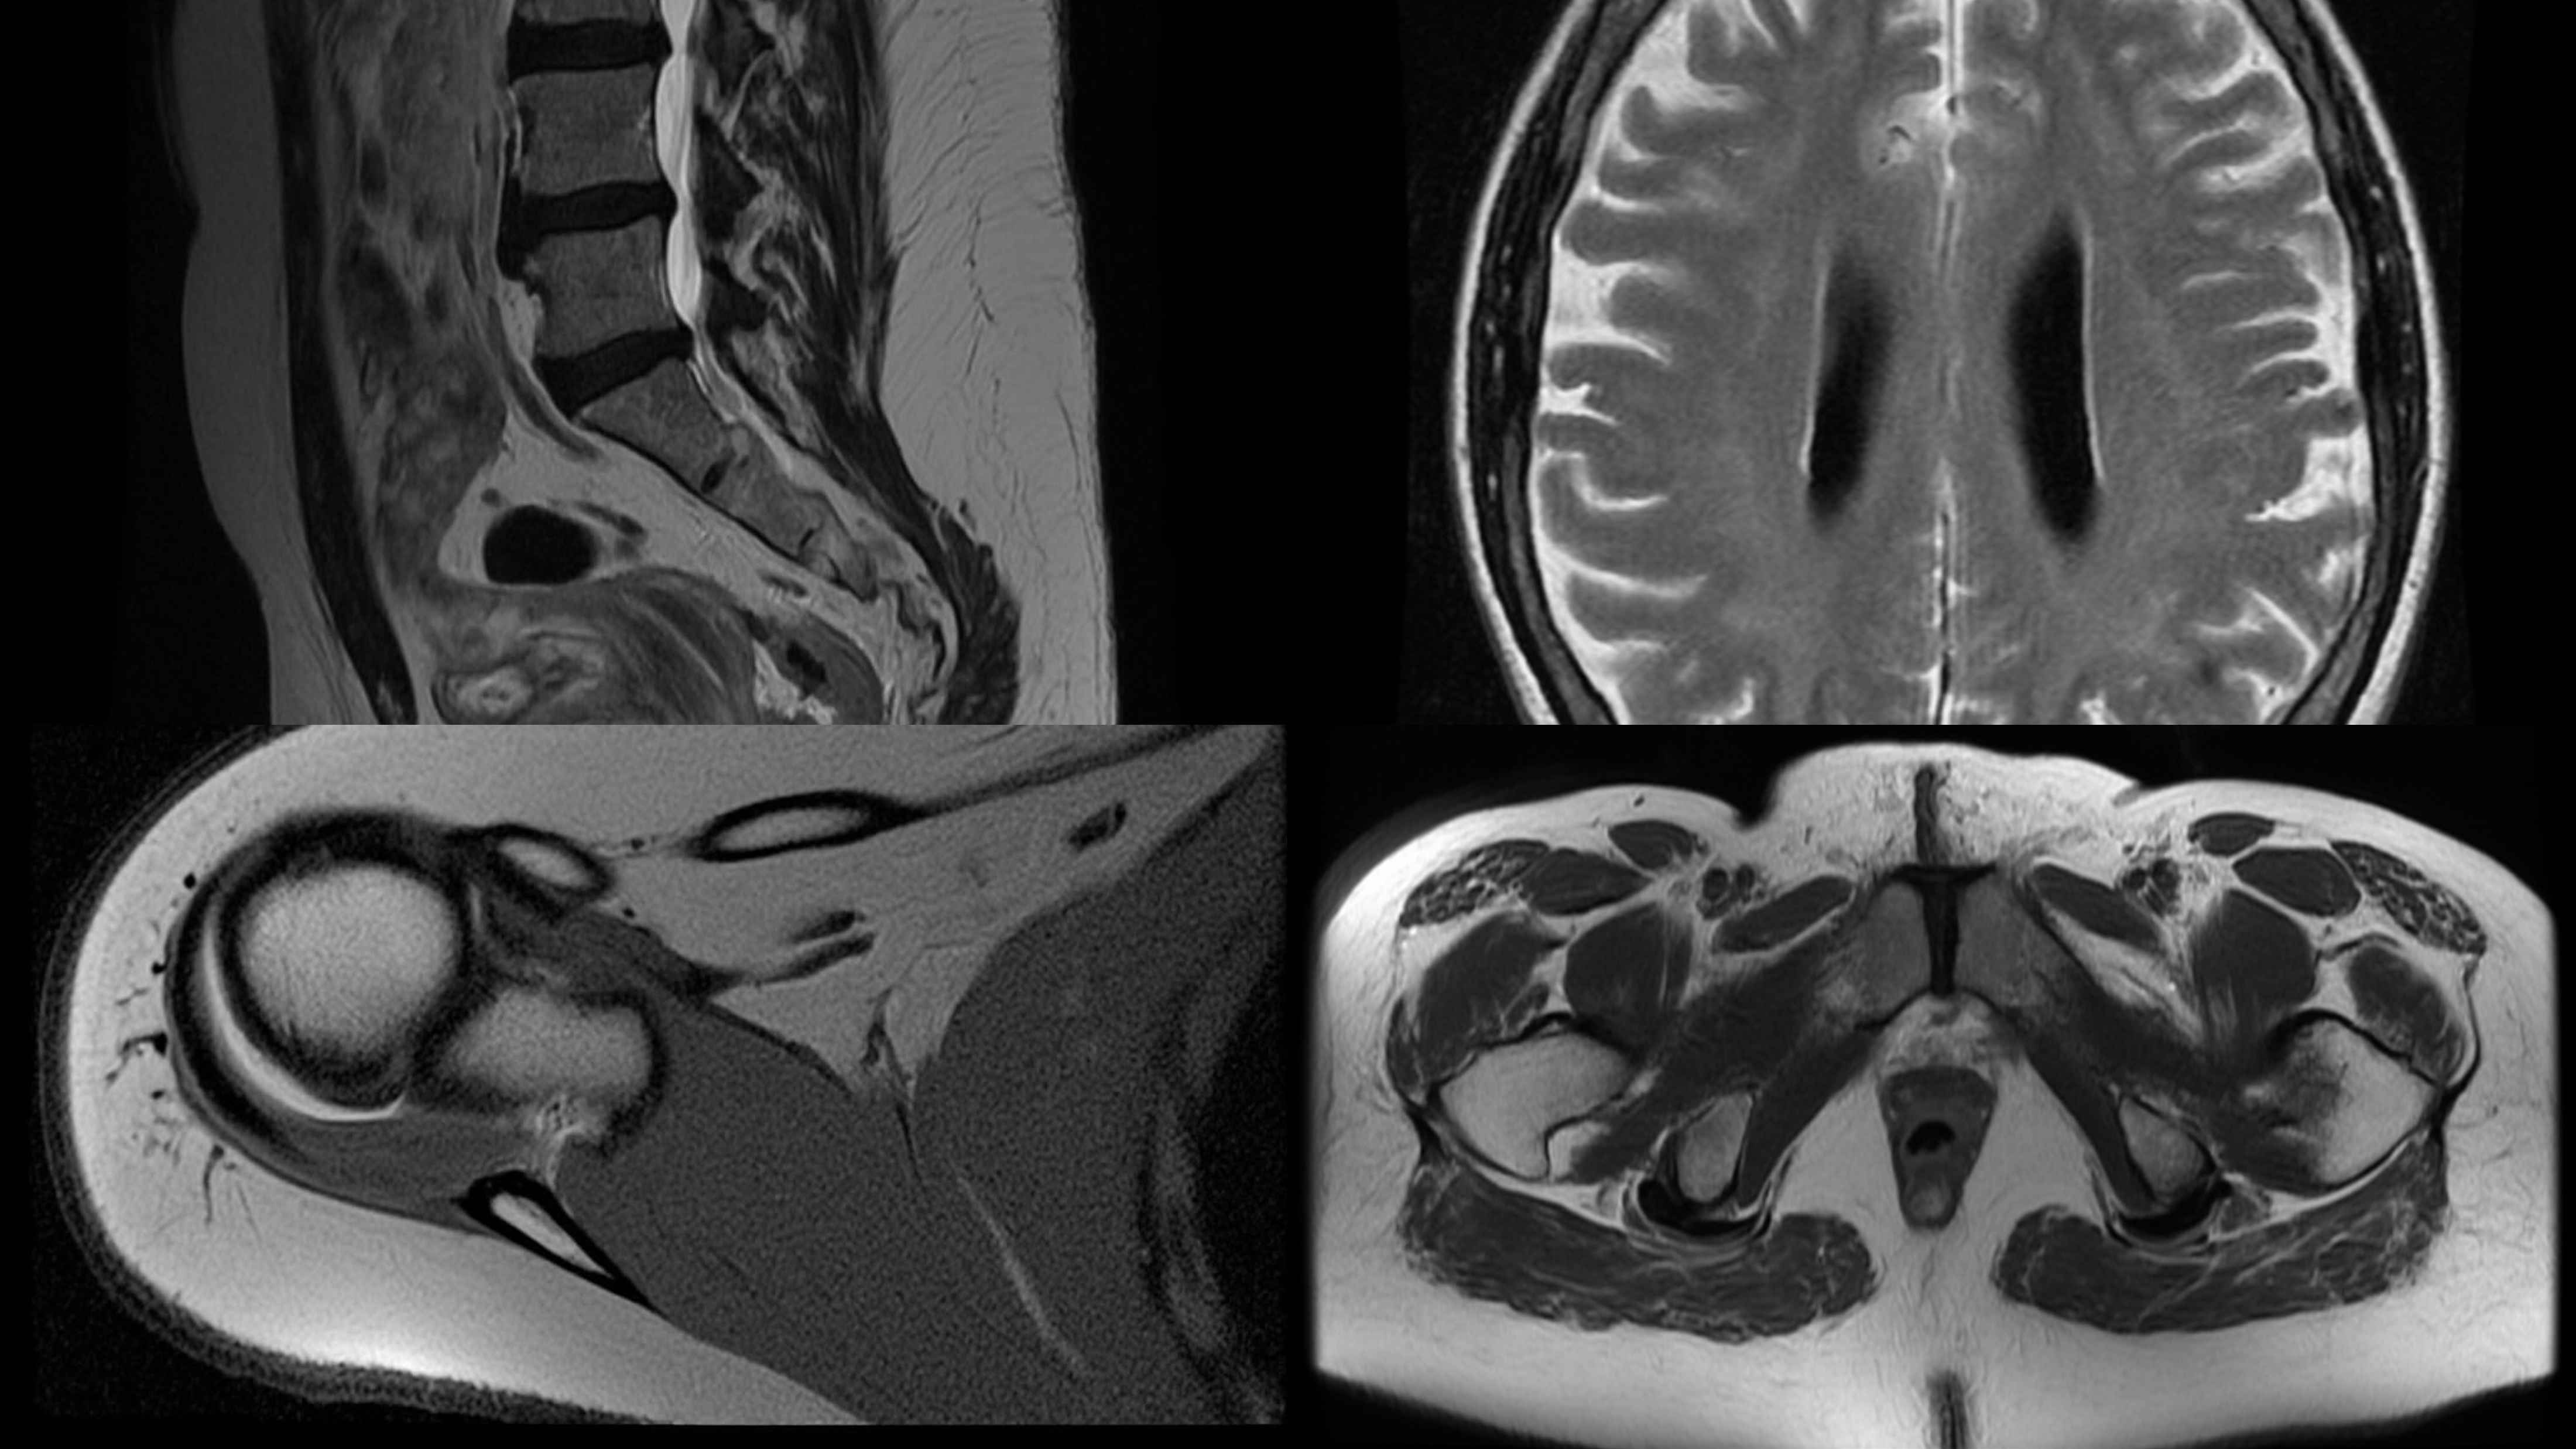

Experimental Results Visualization

Performance Visualization Comparison

Performance Comparison

Comprehensive performance comparison across different training stages and modalities

Multimodal Task Demonstrations

Multimodal Results

Comprehensive visualization of UniMedVL's multimodal capabilities